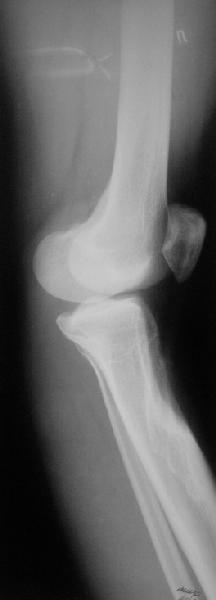

Коллеги из детского отделения направили 18-летнюю студентку с варусно-рекурвационной деформацией проксимального отдела голени.

Жалобы у нее на появившиеся боли в колене при нагрузках. Признаков воспаления не было и нет, опухолевого роста также. Природа дефекта в области бугристости не очень понятна. Дополнительно сделали КТ и боковой снимок в максимальном разгибании - все в приложении.

На какие особенности при коррекции здесь обратить внимание? На какой угол и на каком уровне устранять деформацию? Как быть с переразгибанием в колене? То есть что взять за точку отсчета при устранении рекурвации - максимально возможное сейчас переразгибание, или положение с правильным взаимоотношениями суставных концов? А также готовы принять любые другие соображения, которые Вы полагаете существенными.